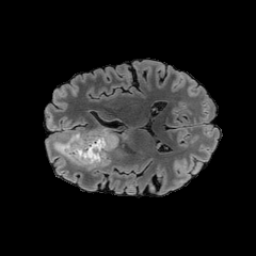

6.3 When does X-Diffusion Fail?

To see when and how X-Diffusion fails, we conducted an experiment on healthy brains (no tumour) using the IXI dataset, by running an X-diffusion trained on the BRATS brain tumor dataset. Our X-Diffusion achieved a PSNR of 35.86 dB on the IXI dataset despite being trained on the BRATS dataset. We then ran the tumour segmenter on the set of 582 healthy scans and corresponding generated MRIs. The segmenter predicted tumours in 9.9% of the real healthy brains and in 11.3% of the generated brain MRIs. Some of these tumor hallucination examples from X-Diffusion generation are shown in Figure 9.

This shows how the generated MRIs indeed preserve the tumour information and can act as an affordable and informative pseudo-MRI, before conducting an actual costly MRI examination in hospitals. Given that our model has been trained on brain scans all with tumours, we expect to see hallucinations of tumours in healthy scans. We report two cases of failure of our model in Figure 16. Hallucinations of tumours on healthy samples represent 2% of the test set.